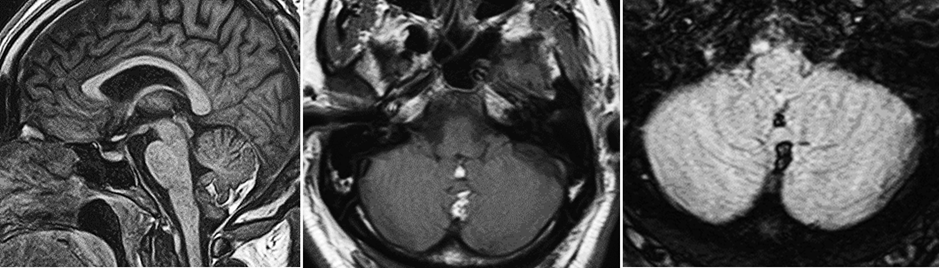

2. A T1-weighted MRI scan was performed.

Explanation: A high signal is observed along the dorsal cerebellum on the T1-weighted MRI images.

Explanation: A High signal is seen at the midline and corresponds to the dorsal cerebellar vermis.

Explanation: The high-intensity signal observed in the T1-weighted MRI matches the characteristics of adipose tissue, which is consistent with a lipoma.

MRI: On T1-weighted MRI, an irregularly shaped high-signal mass is observed along the dorsal vermis of the cerebellum. No infiltration is seen in the cerebellar hemispheres or vermis.

FLAIR: On axial FLAIR MRI, no signal is observed in the same area as the T1 high-signal, consistent with adipose tissue.

Intracranial lipomas originate from the meninx primitiva, an embryologic structure that gives rise to the dura, arachnoid, and pia mater. If the meninx primitiva fails to regress between the 8th and 10th weeks of gestation, it may lead to abnormal differentiation, resulting in a lipoma. Most intracranial lipomas are asymptomatic and found incidentally. The most common locations include the pericallosal region (accounting for approximately 45% of cases), the quadrigeminal cistern (25%), the suprasellar cistern (15%), and the cerebellopontine angle (10%). In this patient, the lipoma is located in the dorsal cerebellar vermis, which is a rare site.

Lipomas are benign malformations and do not infiltrate or metastasize to other structures. Rarely, they may exert mass effect on local structures, particularly if the patient gains weight and the adipocytes within the lipoma enlarge. In this case, although initially asymptomatic, the lipoma could compress the dorsal vermis as it grows, potentially resulting in impaired motor function affecting the trunk and proximal limbs, such as gait ataxia.

Radiologic Summary

• CT: Appears as a non-enhancing mass with homogeneous fat density; peripheral calcifications may be present.

• T1-weighted MRI: Shows high signal intensity.

• T2-weighted MRI: Also shows high signal intensity.

• FLAIR MRI: Signal may be suppressed or absent.